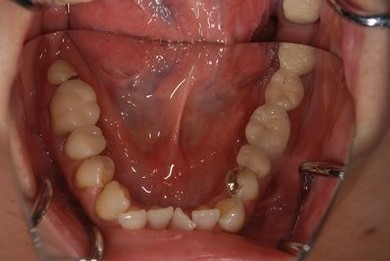

インプラントの症例写真 IMPLANT

骨再生スピードインプラント治療+セラミック治療

| 治療内容 | インプラント9本(抜歯即日スピードインプラント、サイナスリフト)、ハイブリッドセラミッククラウン12本(ハイブリッドセラミック用土台3本) | ||||||||||||||||||||||||||||||||